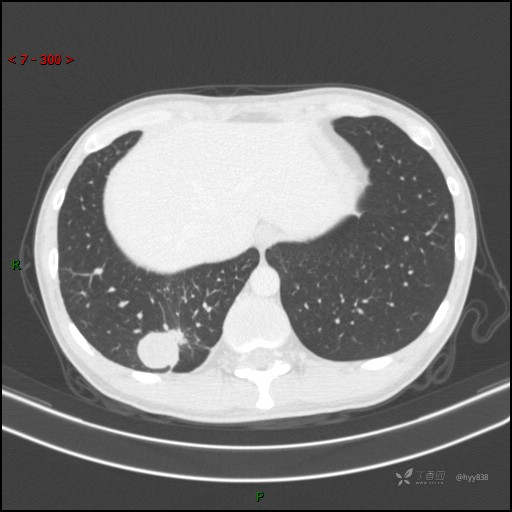

胸部CT平扫